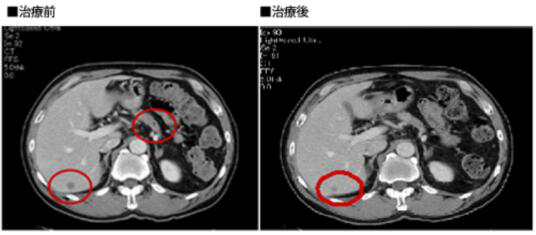

案例1

病名:胰腺癌Ⅳ期,肝转移

患者:66岁男性

疗法:树突细胞疫苗

经过:2008年1月发现,接受1疗程化疗后,3月开始接受WT1、MUC-1、CA125多价树突细胞疫苗

治疗。肿瘤标志物DUPAN2从25,300U/ml降至1,640U/ml。原发灶消失,转移灶缩小。